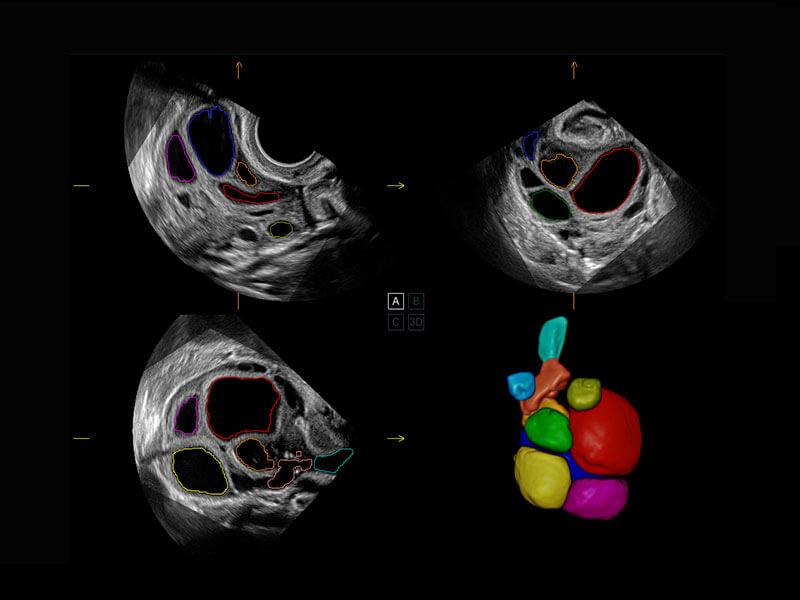

P60为盆底超声检查提供应用方案,多种腔内及腹部容积探头提供从二维、三维到四维的优异图像品质,实时快速三维容积数据获取,专业的测量工具包等人性化设计,为超声医生诊断提供有力保障。

能够简化盆底检查的操作流程,可在二维模式及三维成像模式下实现一键自动提取出标准切面、自动识别当前切面、自动测量,提升盆底检查的高效性,同时也能让青年医生快捷的获得准确的检查结果。